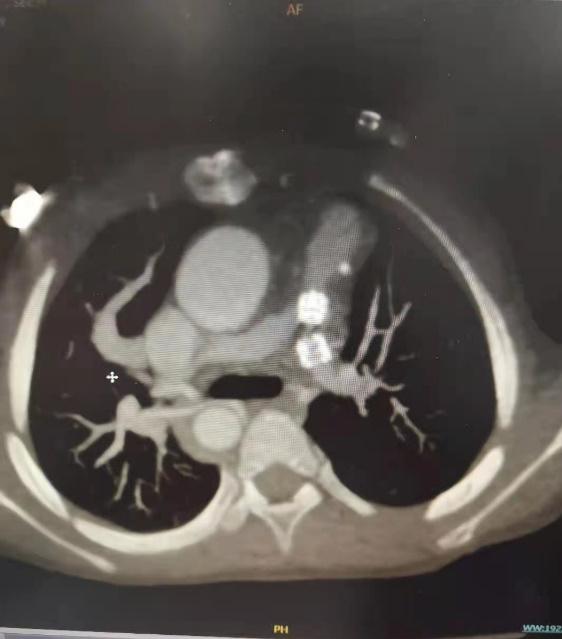

2021年3月9日再次门诊复查行心脏CT提示左肺动脉支架内支架不连续,左肺动脉远端发育小,右肺动脉扭曲,考虑支架断裂,断裂之间的肺动脉严重狭窄。

CTA显示断裂的支架和严重狭窄的左肺动脉